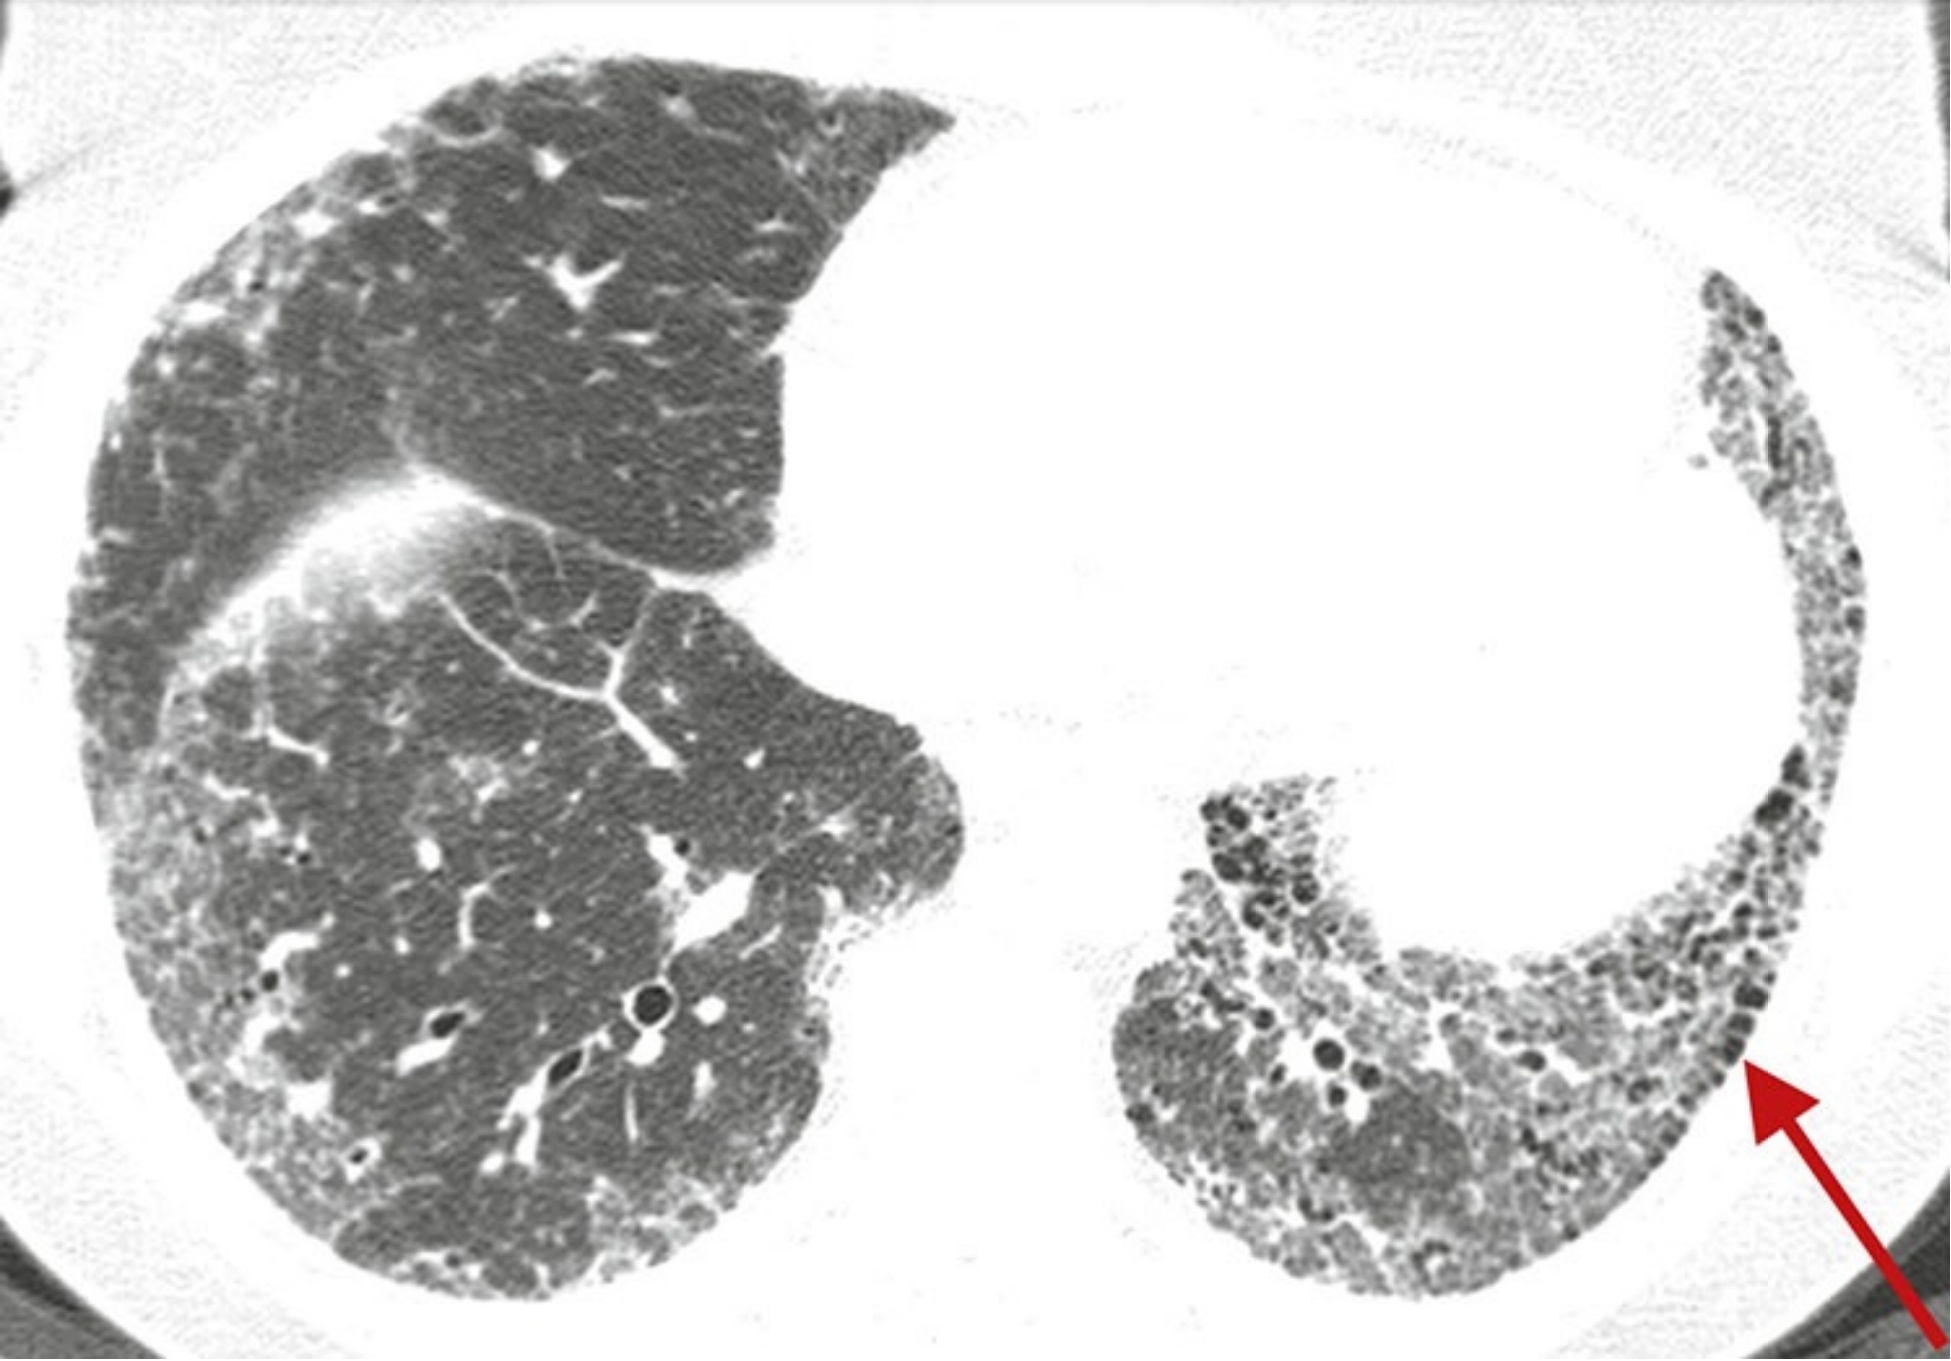

1b4163a751fee4c845315e379d18df02.png

低置信度诊断为UIP。

过敏性肺炎患者,俯卧位HRCT显示肺纤维化不以胸膜下分布为主(A), 且不累及肋膈角(B)。由于病灶以肺中央及上肺分布为主, 故与UIP表现不一致。